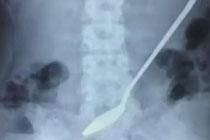

浙江女孩误吞20公分长钢勺 3天后腹痛才去医院